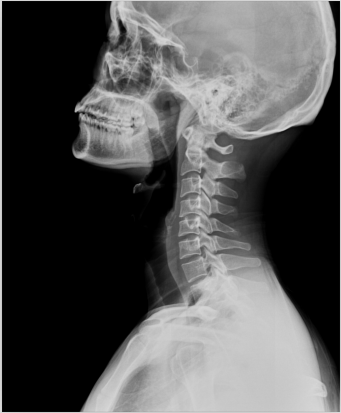

1、外傷骨頭——粗看X光攝影、細(xì)看CT

當(dāng)遇到各種外傷,如果懷疑傷到了骨頭,優(yōu)先選擇X光攝影,檢查結(jié)果快速易得。若要進(jìn)一步觀察,可以選擇CT觀察細(xì)節(jié),甚至磁共振成像觀察隱匿損傷或軟組織損傷。

2、頸椎腰椎——最佳選核磁共振成像、次選CT

頸椎病、腰椎間盤突出等椎間盤疾病需要觀察椎間盤與相應(yīng)的神經(jīng)根,要想更好觀察這些軟組織,最優(yōu)選擇就是磁共振成像。同樣,對于關(guān)節(jié)、肌肉、脂肪組織檢查,腫瘤、炎癥、創(chuàng)傷、退行性病變以及各種先天性疾病的檢查,磁共振成像也是不錯(cuò)的選擇。CT可以作為觀察脊椎骨質(zhì)增生、椎間孔狹窄的有力補(bǔ)充。